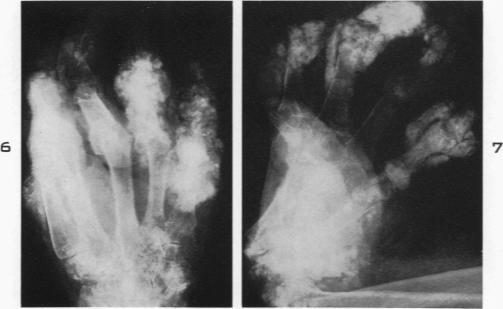

Pathologic changes in gout; survey of eleven necropsied cases.

Am J Pathol. 1956 Sep-Oct;32(5):871-95.